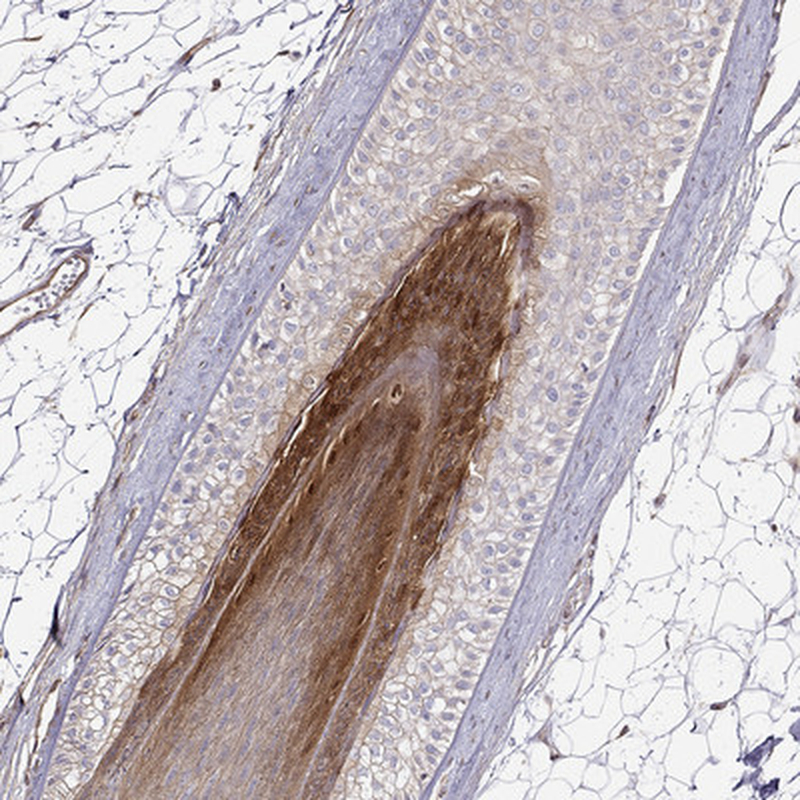

Immunohistochemistry analysis in human skin and pancreas tissues using Anti-GSDMA antibody. Corresponding GSDMA RNA-seq data are presented for the same tissues.